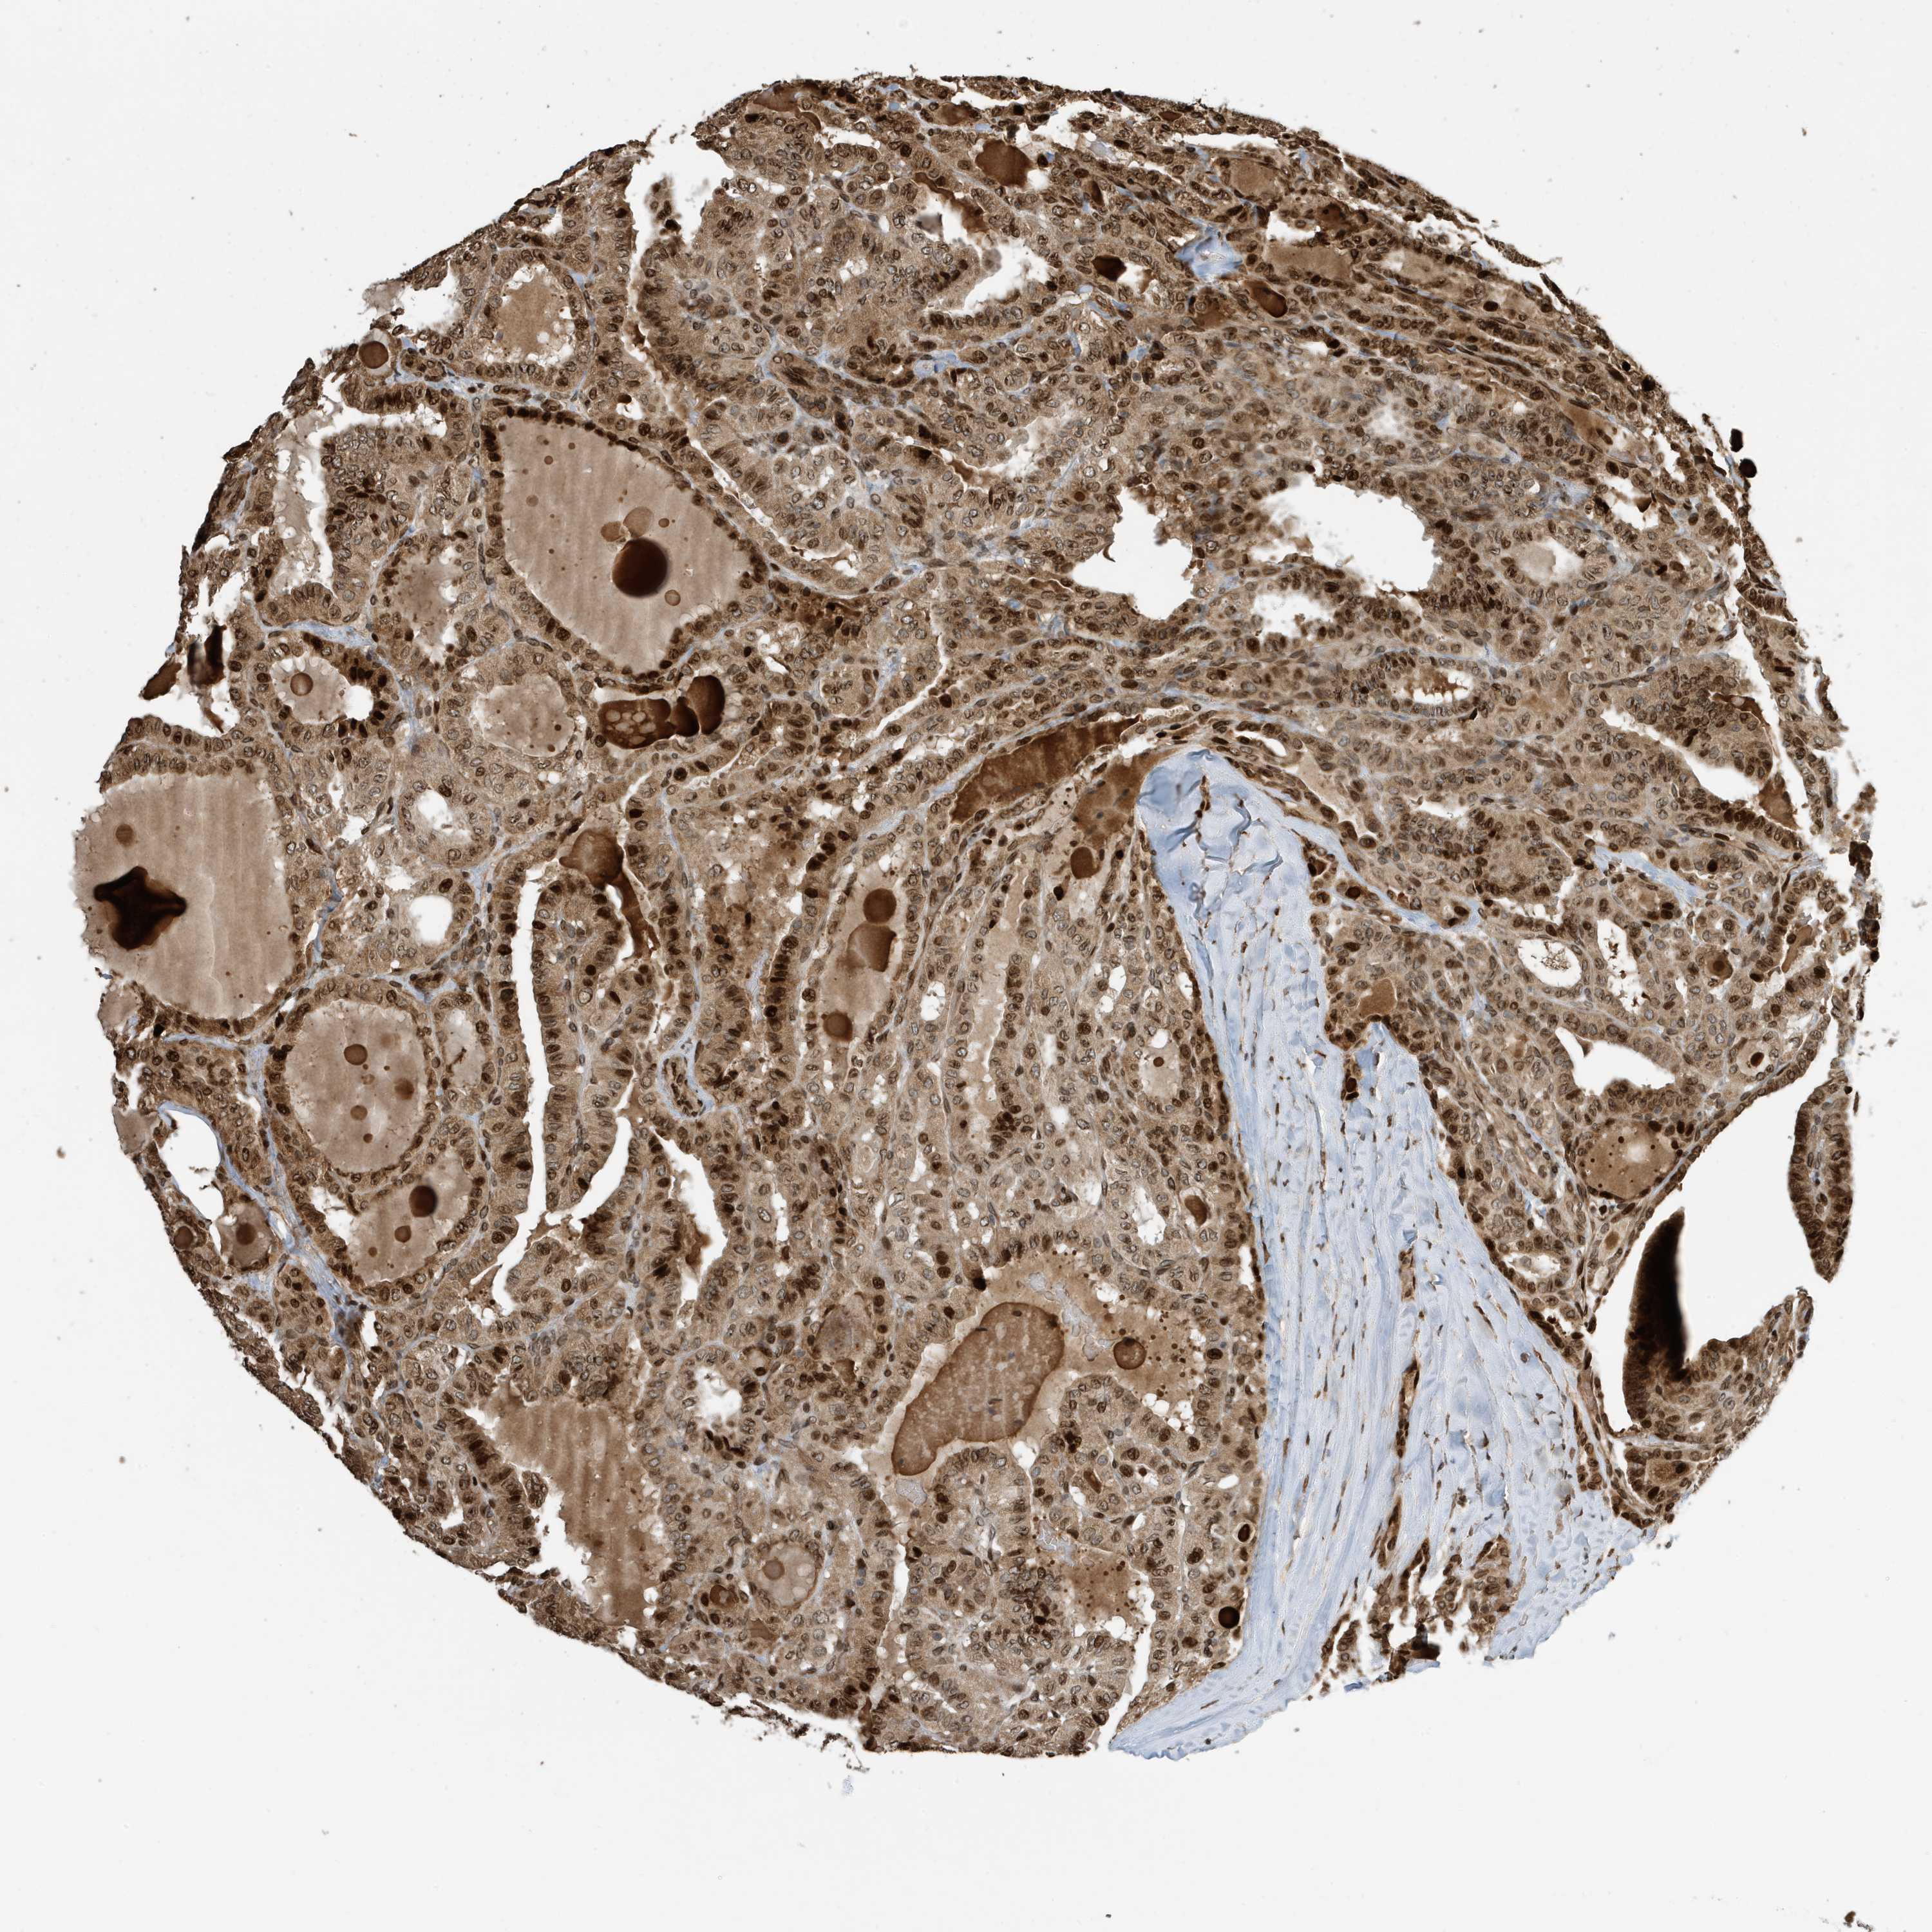

THYROID CANCER - Protein expressioni

A mouse-over function shows sample information and annotation data. Click on an image to view it in a full screen mode. Samples can be filtered based on level of antibody staining by selecting one or several of the following categories: high, medium, low and not detected. The assay and annotation is described here.

Note that samples used for immunohistochemistry by the Human Protein Atlas do not correspond to samples in the TCGA dataset.

Antibody stainingi

Antibody staining in the annotated cell types in the current human tissue is reported as not detected, low, medium, or high, based on conventional immunohistochemistry profiling in selected tissues. This score is based on the combination of the staining intensity and fraction of stained cells.

Each image is clickable and will lead to virtual microscopy that enables deeper exploration of all samples and also displays staining intensity scores, fraction scores and subcellular localization as well as patient and tissue information for each sample.

Antibody CAB034070

Staining

High

Medium

Low

Not detected

Intensity

Strong

Moderate

Weak

Negative

Quantity

>75%

75%-25%

<25%

None

Location

Nuclear

Cytoplasmic/membranous

Cytoplasmic/membranous,nuclear

Papillary adenocarcinoma, NOS

Follicular adenoma carcinoma, NOS